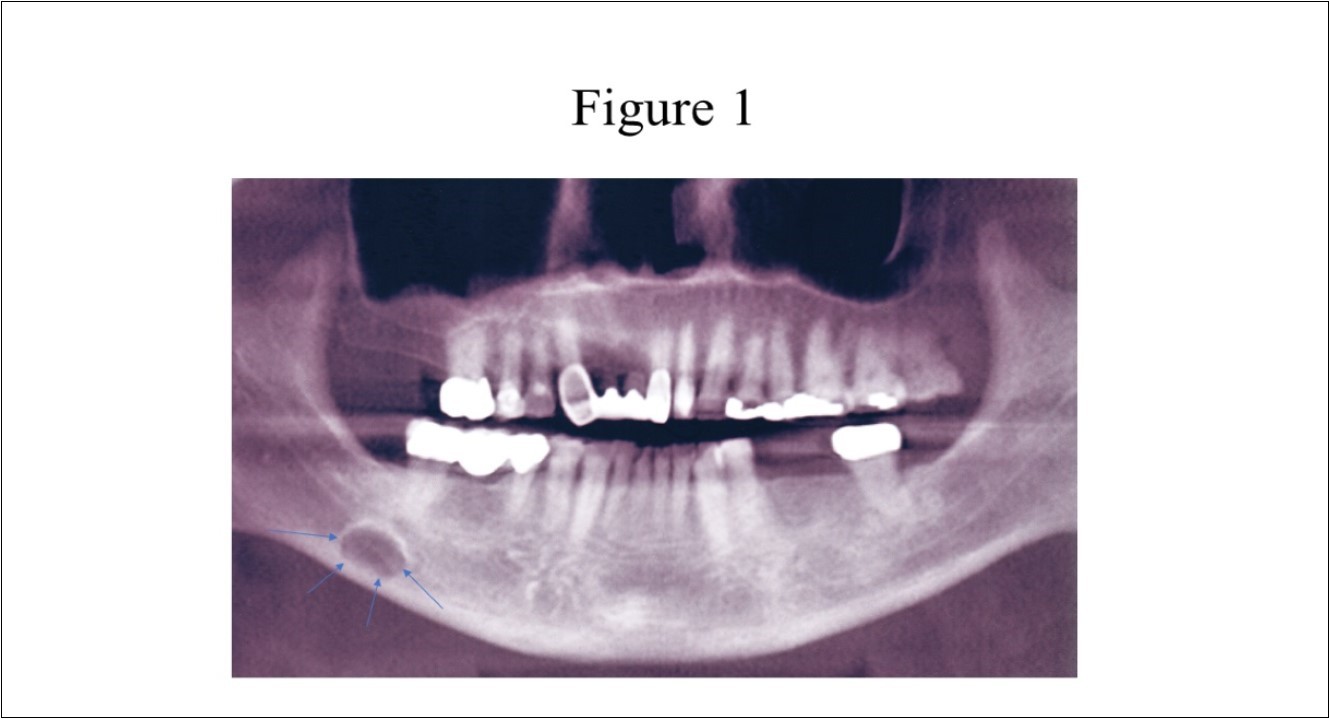

Radiographic features (Figure 1) of the SBC are a well-circumscribed unilocular, round or elliptical shaped radiolucency in the posterior mandible that are approximately 10 to 30mm in length. 1,3,4The radiographic lesion is often incidentally discovered when the patient completes a routine panoramic radiograph at the dentist office and does create concern for the dentist as it can mimic a cystic lesion.3,5,6

Figure 1.Panoramic radiograph of classically described SBC of the right posterior mandible illustrates the well-defined unilocular radiolucency in the right posterior mandible between the inferior alveolar canal and the inferior border of the mandible (arrows).